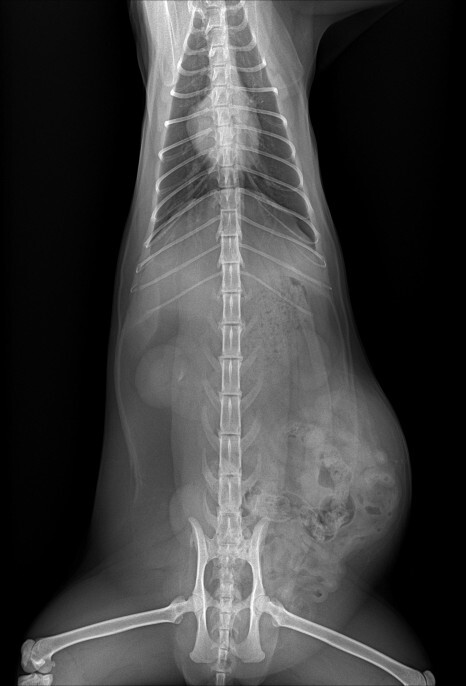

방사선 및 복부 초음파

이 아이의 경우 육안으로도 확연하게 확인이 가능할 정도로 서혜부쪽의 배가 볼록하게 나와있었습니다.

정확한 상태를 파악하기 위해서 엑스레이와 복부 초음파 검사를 하였습니다.

서혜부 탈장이 확인 되었고 수술을 진행하기로 결정하였습니다. 아이는 며칠 동안 입원하여 안정을 취하기로 하였습니다.